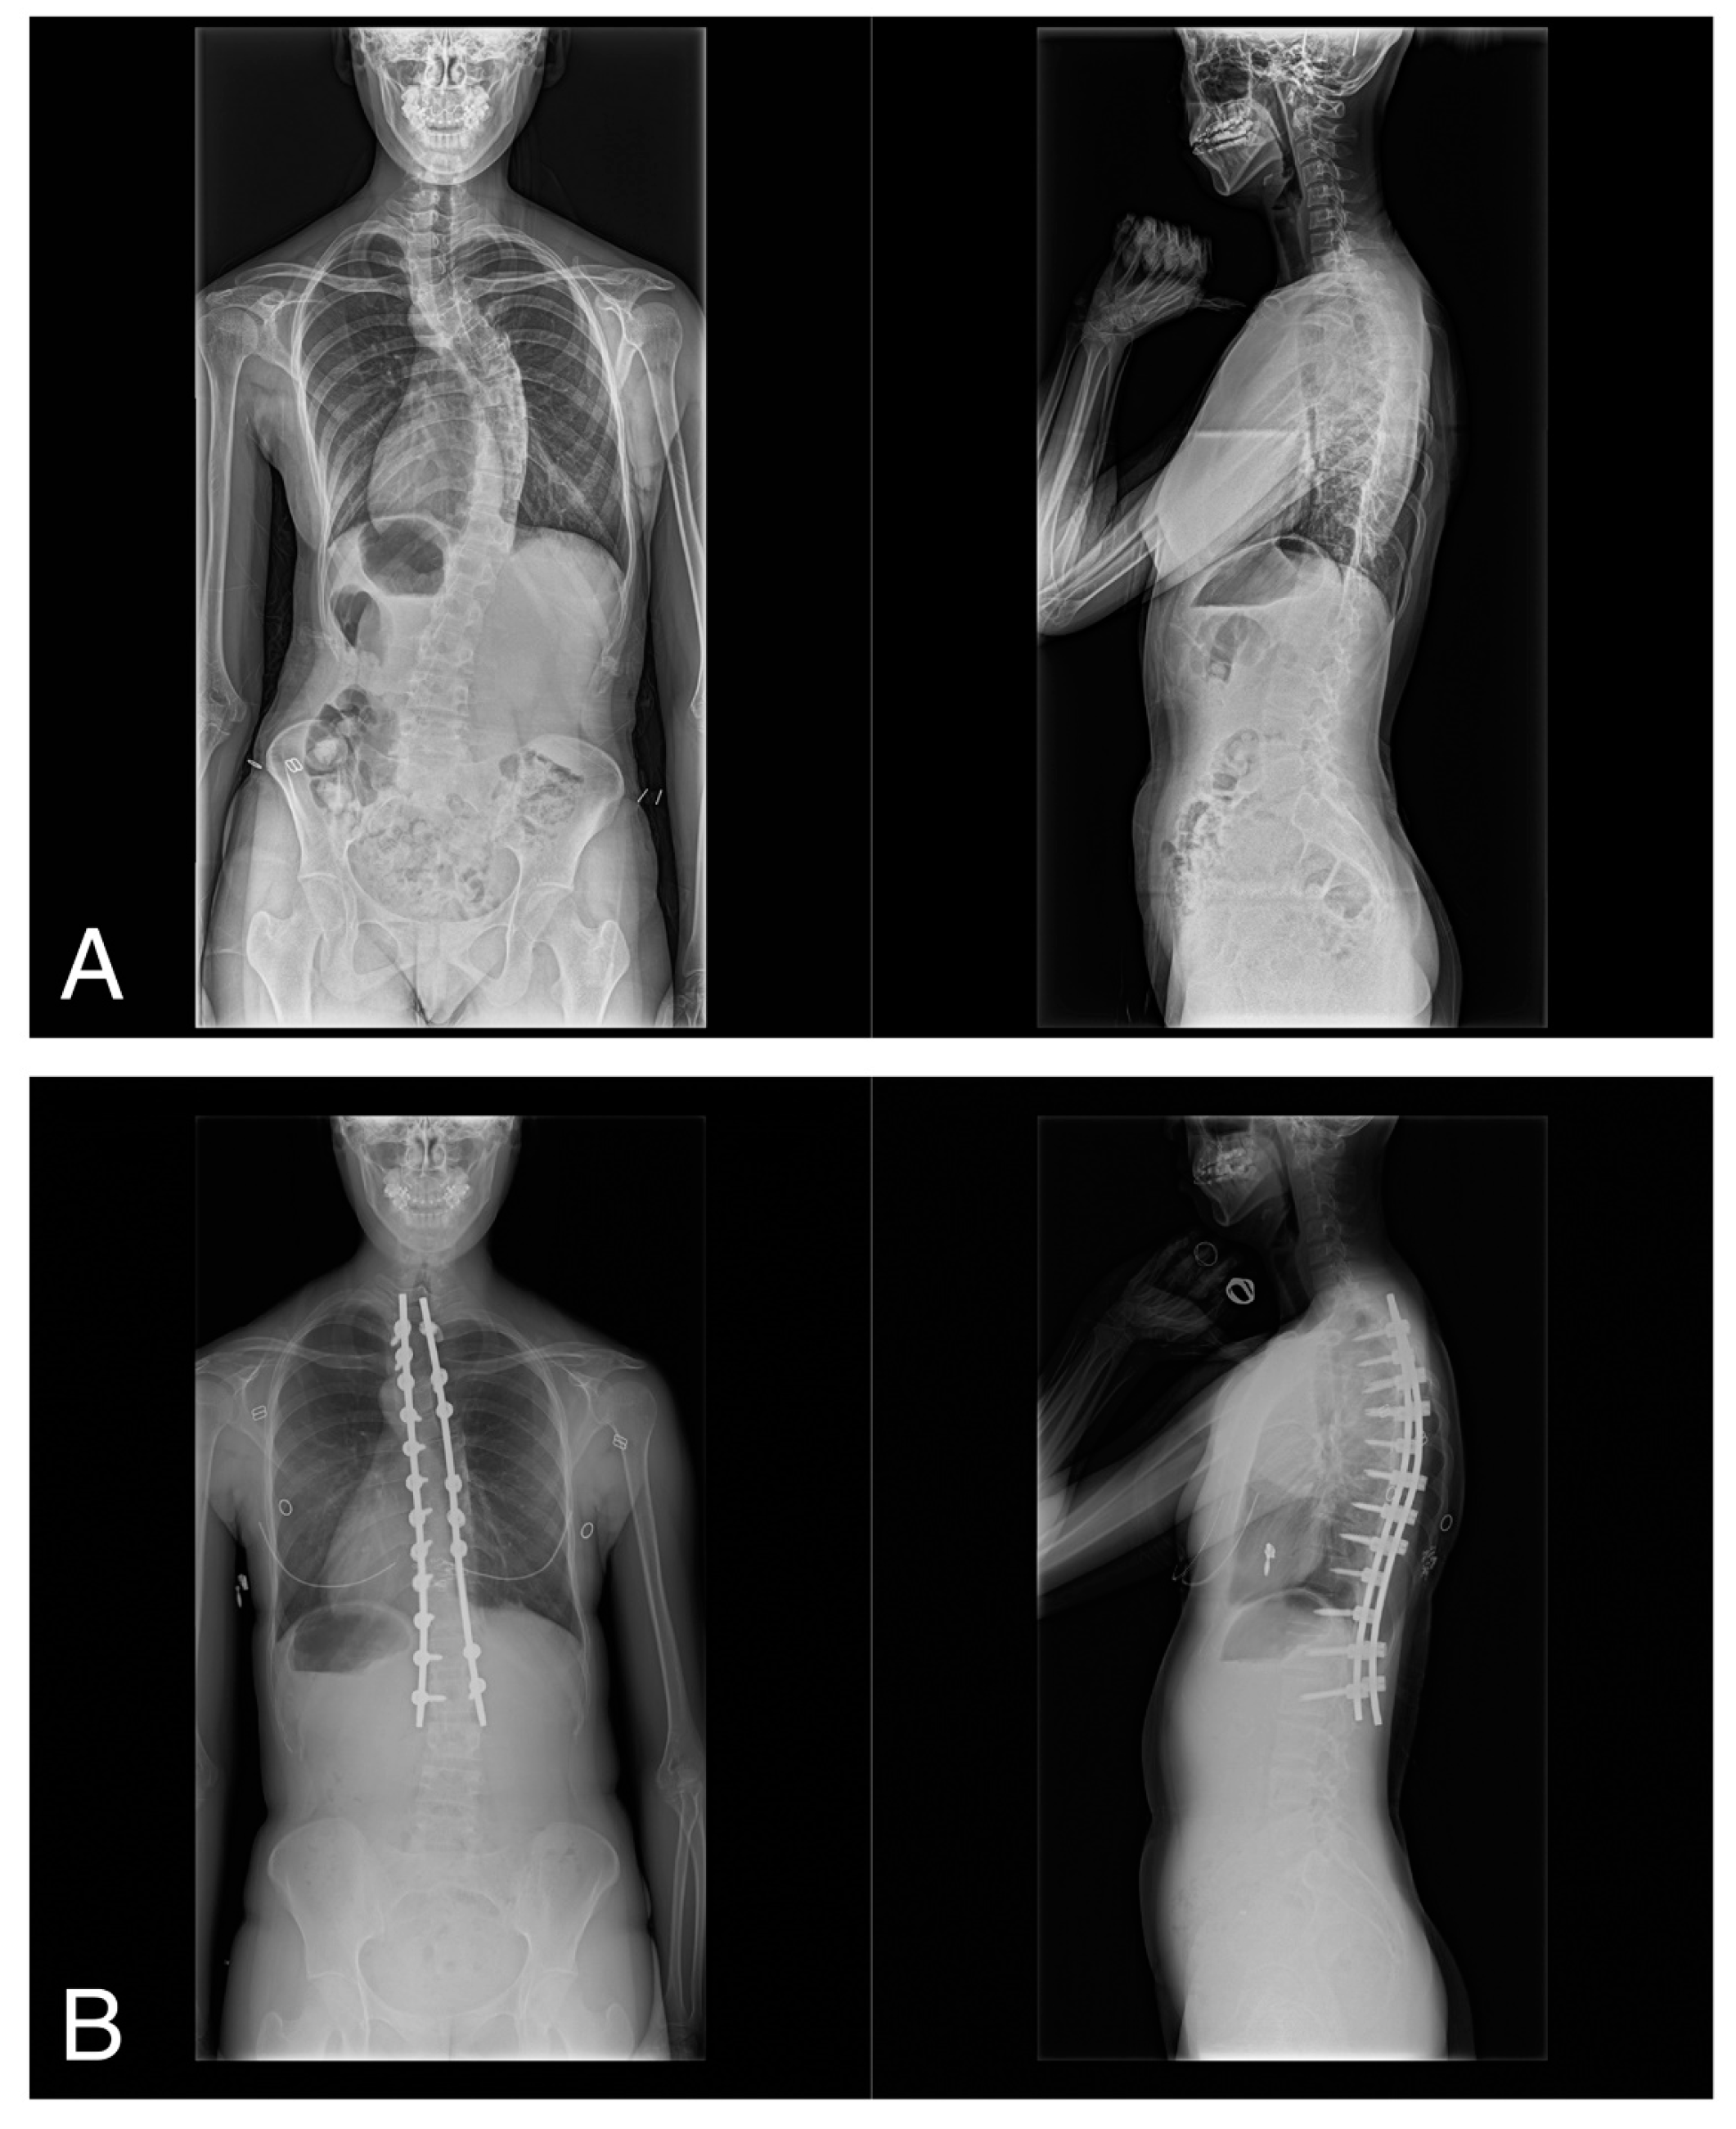

A consecutive group of 33 female patients diagnosed with AIS and categorized into different Lenke types (1A, 1B, 1C, 2A, 3C, and 4C) participated in this study (Table 1). All patients underwent posterior spinal correction and fusion using the 4D anatomical spinal reconstruction technique for AIS correction (Figure 1) [9]. Patients with syndromic, neuromuscular, or congenital scoliosis were excluded from the study. Furthermore, to maintain the focus on the 4D anatomical spinal reconstruction technique, patients with Lenke type 5C AIS, which refers to the main thoracolumbar/lumbar AIS curves, were excluded from the study. The number of participants in the present study was calculated based on the TTB data previously collected during single-leg standing [14]. Sample size calculations showed that a minimum of 19 patients would be required to detect a change in the mean TTB value after surgery (α = 0.05, 1 − β = 0.80).

Figure 1.

(A) Preoperative anteroposterior and lateral views of a 17-year-old woman with Lenke type 1A scoliosis, and (B) anteroposterior and lateral radiographs at 2 years postoperatively.